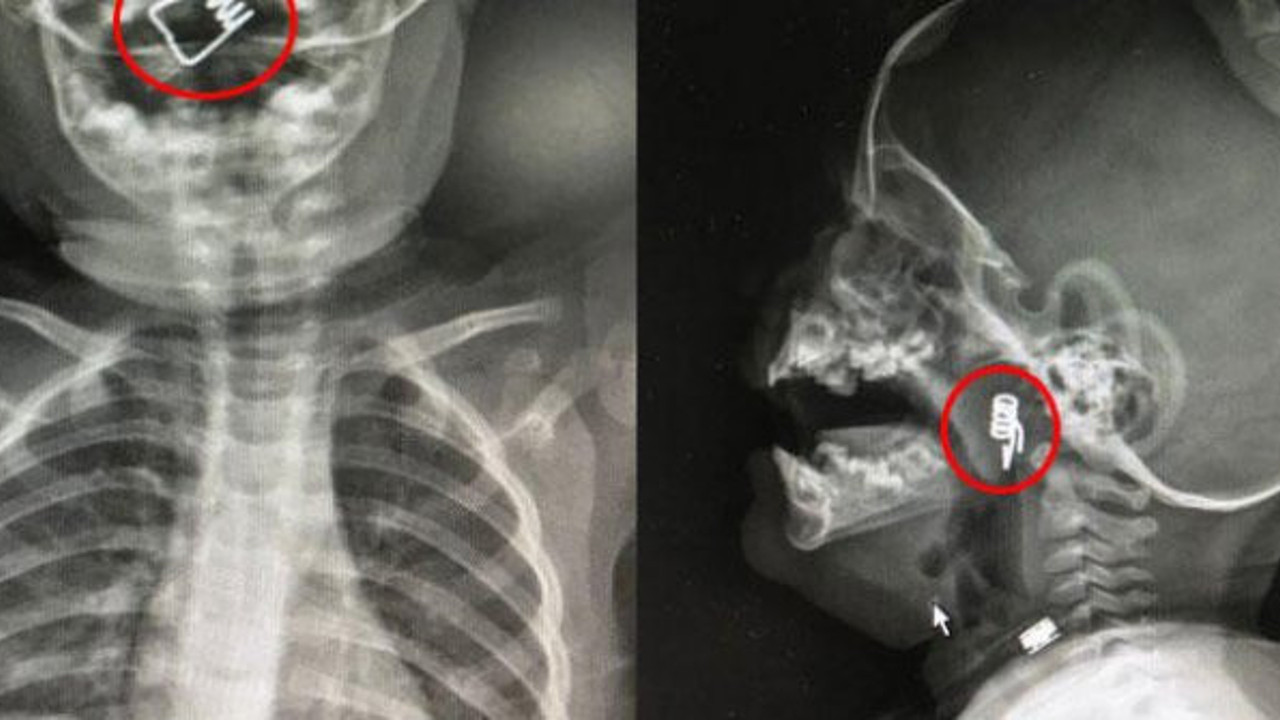

Nevşehir'de 1 yaşındaki erkek bebek Ö.Y., dün akşam saatlerinde elinde mandalla oynarken, parçalanan mandalın yayını ağzına aldı. Duruma müdahale eden bebeğin babası, yayı çocuğunun ağzından çıkarmaya çalışırken, yay bebeğin genzine kaçarak saplandı. Nevşehir Devlet Hastanesi Acil Polikliniği'ne getirilen bebeği, Acil Nöbetçi doktoru Mustafa Alpaslan muayene ederek gerekli tetkikleri yaptı. Çekilen röntgen filmlerinde mandal yayının lokalizasyonu ve durumu belirlendi. Daha sonra, KBB Uzmanı Op. Dr. Ahmet Cevatzade tarafından yapılan başarılı ameliyat sonucunda bebeğin genzine saplanan mandal yayı çıkartıldı.